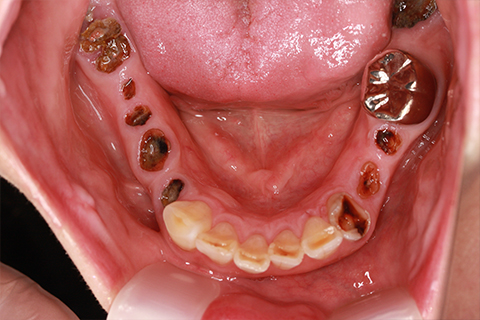

症例5

- 年齢・性別

- 35歳男性

- 治療期間

- 3ヶ月

- 抜歯

- 右上1.3左上6.7の残根抜歯

- 治療費

- 132万円

- 備考

- 右上1.3左上6.7の欠損部

- 治療内容

- 4本のインプラントを一回のオペで埋入。

- 施術の副作用(リスク)

- オペによる知覚障害。インプラントによる歯肉炎。インプラント脱落。